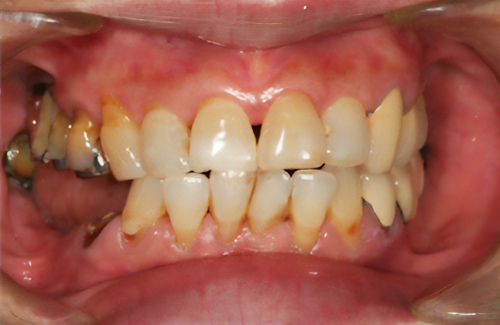

歯の形、歯並び、歯肉ラインが整う美しい口元

大掛かりな歯ぐきの手術や装置を使った矯正治療を行わずに、たった2回で歯並びをきれいに整えることができます。

術前

術後

BTAテクニック® とは

従来のセラミックで治すオールセラミックという被せ物や、セラミックを張り付けるラミネートべニアという方法に、歯科医師と歯科技工士の双方の手法と技法を癒合させることで、可能とした 歯ぐきのラインを2回の来院で、綺麗に仕上げ、歯の見た目も審美的に出来るテクニックのことである。

BTAテクニック® 以外の一般的な治療で歯ぐきのラインを整えるには、歯ぐきを切り、骨を削る手術をすれば可能ですが、歯ぐきの治りに数か月の期間が必要です。もしくは、矯正治療によって、歯並びを改善する方法、もしくは神経を抜いて、被せ物をするしかありません。

BTAテクニック® を用いると、歯ぐきや骨への手術が必要ない為に、治療期間が短縮でき、2回の来院で完了できるメリットがある。 また、この方法を用いることで、年々歯ぐきが下がって見た目が悪くなるということが起きにくくなる。歯周ポケットと言われる溝が浅くなり、歯ブラシが容易になる。などの利点が挙げられる特殊なテクニックである。